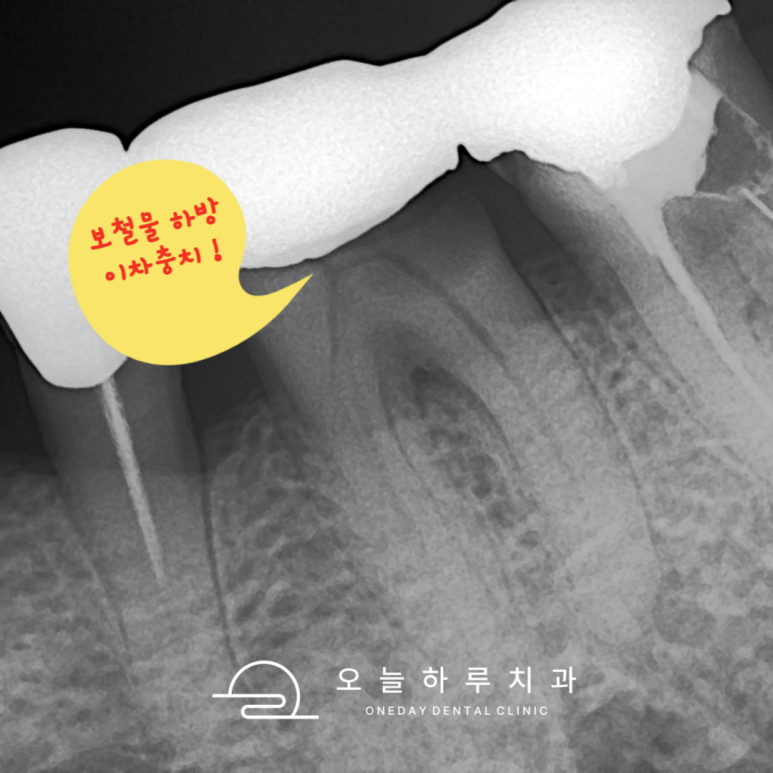

🦷 3. 보철물 문제 (인레이/크라운)

- 원인: 오래된 보철물, 경계 불량, 2차 충치

- 증상: 씹을 때 자극, 안쪽 통증

- 치료:

- 보철물 제거 후 충치 확인

- 재보철 또는 신경치료